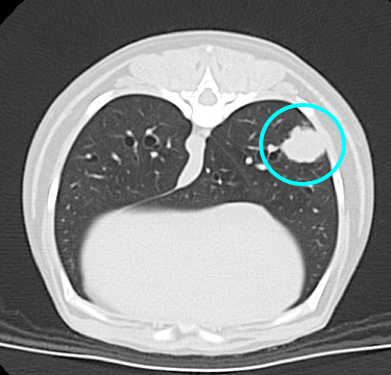

レントゲン検査所見より肺腫瘤を疑い、CT撮影検査と超音波ガイド下での経皮的針生検を麻酔下で同時に行ないました。

CT撮影検査では右肺後葉に長径1.5~2.0cm程度の腫瘤性病変が確認され、細胞診検査により上皮系悪性腫瘍が疑われました。

画像中央肺野に腫瘤が確認されます。